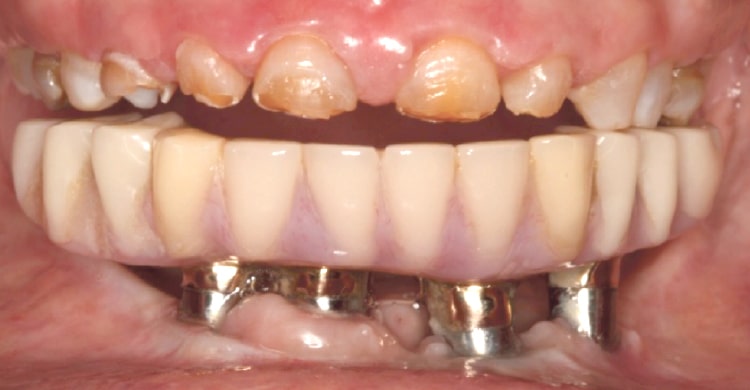

当院には、オールオン4治療で失敗してしまった患者さんが多数相談に来られます。そのほとんどが、他医院の格安なオールオン4治療を受けた方です。

インプラントのトラブルでご来院された患者様の症例写真。インプラントを除去せざるを得ませんでした。

〜顎の力との調和〜顎の力は非常に強いため、噛むことによって生じる力と上部構造との調和が取れていなければなりません。調和が取れていなければ力に耐えきれずに壊れてしまう場合があります。治療計画・シミュレーションの精度がオールオン4の成功を左右します。

アクセスホールの位置

インプラント体と上部構造を連結するための穴を「アクセスホール」と呼びます。オールオンフォーでは、一般的に4つのアクセスホールを作成しますが、この位置関係が極めて重要になります。

インプラントの埋入位置について、事前に十分なシミュレーションを行っていない場合、その場凌ぎ的に不適切な箇所にアクセスホールを作ることになります。術前の診査・診断・プランニング、咬合力の強さや補綴物のスペースを考慮した治療計画を作成し、ガイデッドサージェリーによってインプラント埋入を行えば、このようなミスは決して発生しません。